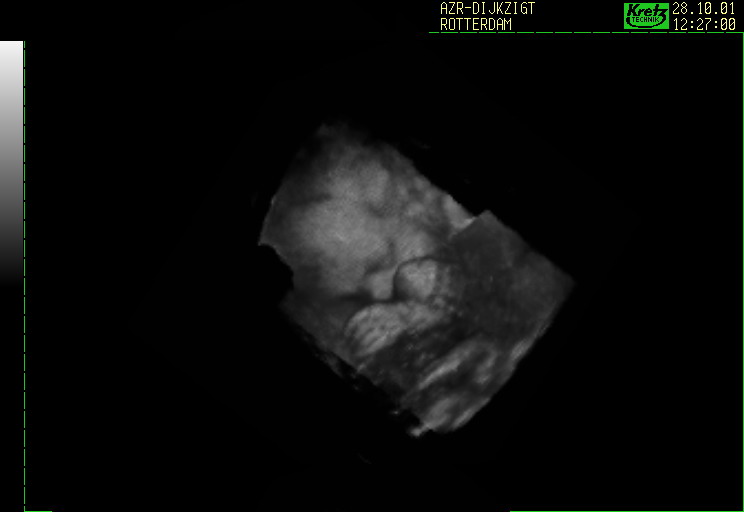

Sin embargo, cuando la ecografía se realiza en un departamento de ginecología, su función es verificar la posición, la salud y otros aspectos del bebé. Además, la tecnología 2D se utiliza para proporcionar dos dimensiones de la imagen. Si bien se usa el uso de la tecnología 3D, revela las mismas imágenes en 3 dimensiones que son más claras y prominentes que las 2D. Además, la tecnología 4D lo deja más claro que todo. Además, hace que los pacientes puedan ver las imágenes en movimiento. Incluso, en etapas posteriores de su embarazo, pueden ver los movimientos de su hijo, como sonreír y bostezar. La técnica ultrasónica también ayuda a evaluar si el niño está pasando por algún tipo de anormalidad y se hace la planificación para tratarla.

Las ecografías 2D, 3D y 4D de ginecología se realizan para evaluar el estado y la posición del bebé. Un ultrasonido 4D muestra un video en vivo de los movimientos del bebé dentro del útero. Entonces, muestra al bebé abriendo y cerrando los ojos y chupándose el dedo, etc.

Tanto los ultrasonidos 3D como los 4D pueden proporcionar imágenes tridimensionales del bebé. Si bien una ecografía 4D es esencialmente una ecografía 3D en movimiento en vivo, proporciona información más detallada sobre el bebé. Puede ayudar a diagnosticar varias diferencias congénitas.

Todos los ultrasonidos 2D, 3D y 4D de ginecología brindan una visión del bebé y detectan cualquier problema con él / ella. Sin embargo, un ultrasonido 4D es el más avanzado que muestra un video tridimensional en vivo del bebé. Permite la evaluación en tiempo real de la cara del bebé.